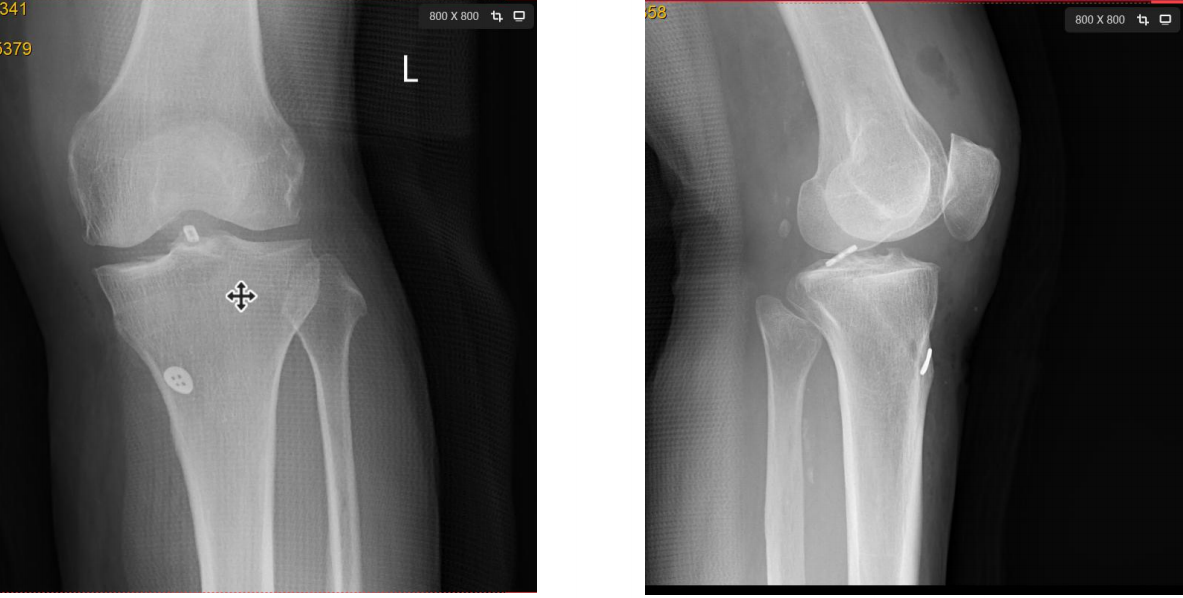

术后X线片